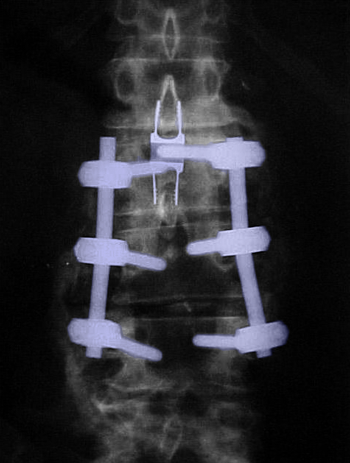

Κάταγμα Ο1 σπονδύλου (κόκκινο περίγραμμα), οπίσθια διαυχενική σπονδυλοδεσία Θ12-Ο3.